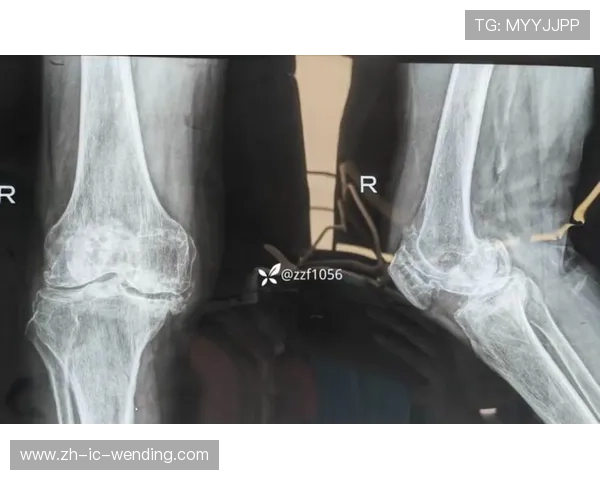

穆迪此次遭遇的是**髌腱伤病**,具体为髌腱撕裂。在职业体育领域,尤其是篮球运动中,髌腱问题一直是困扰运动员、特别是那些依赖爆发力球员的常见伤病。不过,科尔透露的“无软骨骨骼损伤”这一信息至关重要。这意味着损伤主要集中在肌腱组织本身,而并未波及到与之紧密相连的髌骨(膝盖骨)关节面软骨或骨骼结构。

这种相对“单纯”的肌腱损伤,直接影响了手术方案的制定。科尔在采访中证实,由于没有其他复杂结构的损伤,**穆迪将要接受的手术将相对简化**。这通常指向一个更为直接和标准化的肌腱修复或重建程序。简化手术不仅意味着手术过程本身的风险和复杂性降低,更重要的是,它为术后更可预测、更顺畅的康复进程奠定了坚实基础。手术的简化,是医疗团队在全面评估后给出的积极信号。